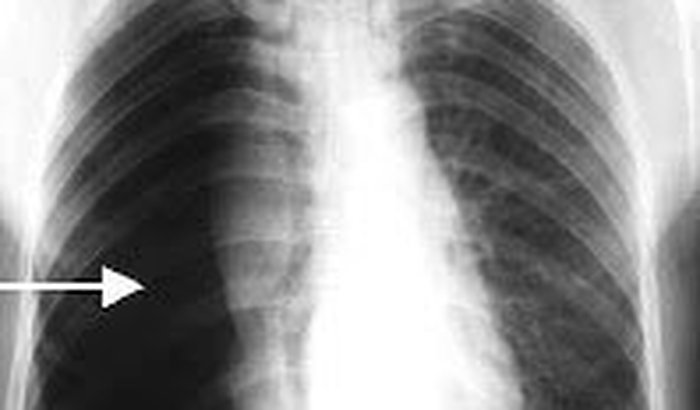

Depois da minha formação do TG tive uma má sorte na vida , conheci uma doença chamada "Pneumotórax Expontâeno" que ao sair de um banco , "Caixa Economica Federal" passei mal , começei a sentir muito dores forte no pulmao , e muito falta de ar , a sensação das vista escurecendo. Fui socorrido a tempo ...Quer saber mais? Assista o vídeo!